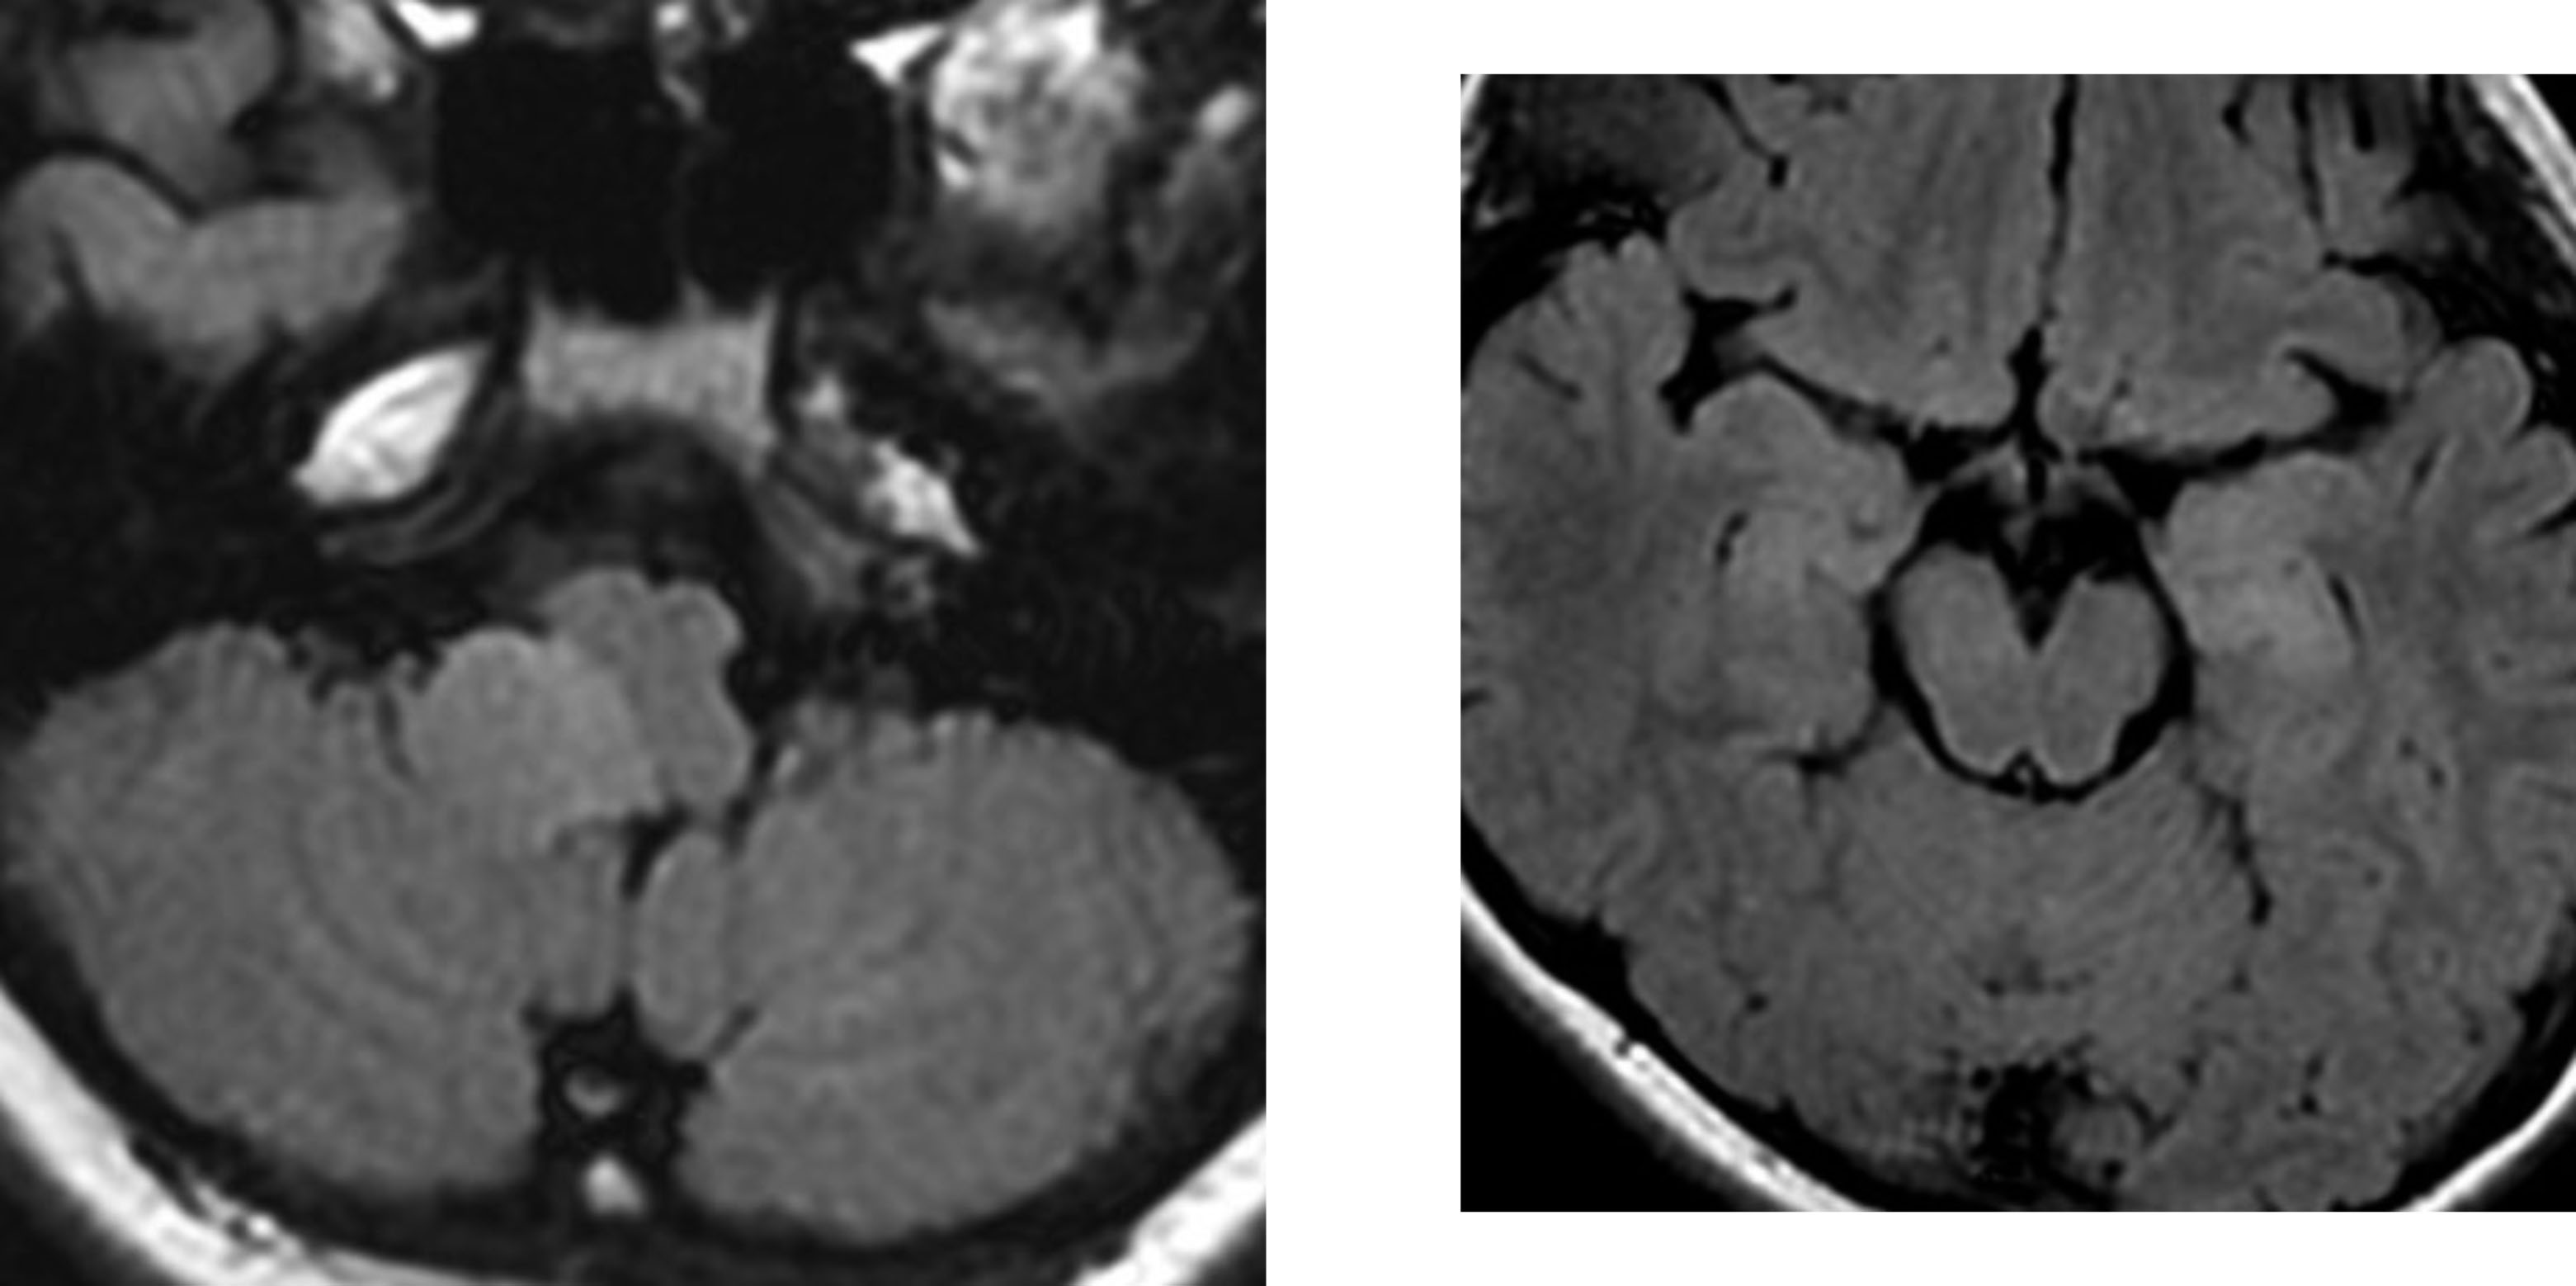

10歳のNF-1の子どもに発見された延髄のグリオーマ

10歳の時のMRI

延髄(左の写真)と中脳(右の写真)にFLAIR画像で病変が見られます

11歳の時のMRI

延髄の病変(左側)だけが増大していますが,あわてて治療しません

14歳の時のMRI

延髄の病変は4年間大きくなり続けていますが我慢して経過観察をします,このような時に,組織を採ってみないと診断がつかないと言われて,生検手術などをされてしまうことがあります(>_<)

逆に中脳(左の写真)の病変は消失しました

16歳の時のMRI

2年の間に延髄の腫瘍はかなり小さくなりました,これを自然退縮 spontaneous involusion と言います